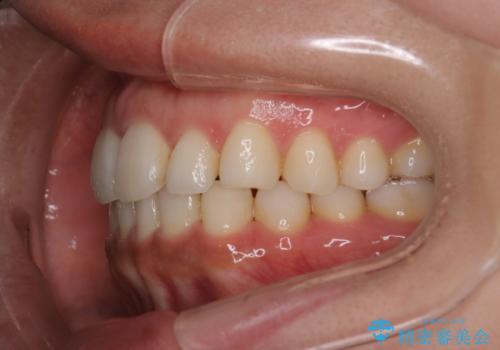

【インビザライン】前歯の後戻りを再矯正

- 前歯が出ていることを主訴に来院されました。検査の結果、口元が標準より出ているわけではなかったため今回はIPRと拡大をし、非抜歯で治療を行いました。

非抜歯でも歯軸の向きを改善したことで前歯が下がり、出っ歯に見えてしまうという主訴が改善しました。